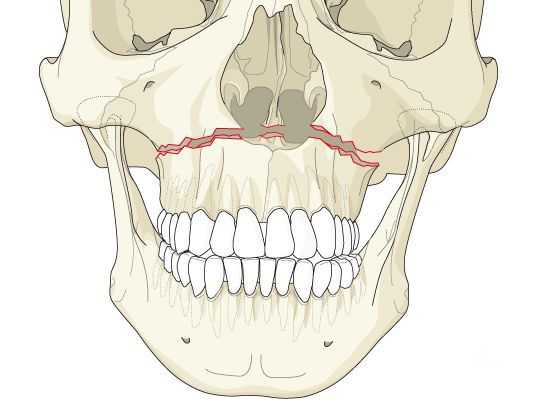

Перелом верхней челюсти — это полное или частичное нарушение анатомической целостности верхней челюсти под действием нагрузки, превышающей её прочность.

Классификация и стадии развития перелома верхней челюсти

Чаще всего переломы классифицируют по Рене Ле Фору. Этот французский хирург систематизировал и описал формирующиеся повреждения костей средней зоны лица экспериментально: на головы свежих человеческих трупов он оказывал разные по направлению и силе воздействия по типу тупой травмы. Именно так и было обнаружено, что большинство линий переломов проходит по трём типам [1] :

- | тип — нижний, или горизонтальный тип, перелом Герена — Ле Фора. Перелом проходит над альвеолярным отростком и нёбным отростком через боковую и переднюю поверхности верхней челюсти, от крыловидных отростков основной кости к краю грушевидного отверстия.

- || тип — средний, или пирамидальный перелом, суборбитальный перелом. Линия перелома проходит через корень носа, внутреннюю стенку глазницы и далее — через нижнеглазничную щель кпереди по нижней стенке глазницы к месту альвеолярно-скулового контрфорса с переломом крыловидных отростков. Проще говоря, верхняя челюсть единым блоком "отсоединяется" от остальных костей средней зоны лица.

- ||| тип — верхний тип (поперечный, суббазальный, он же черепно-лицевое разъединение). Самый грозный вид перелома верхней челюсти, когда происходит отрыв верхней челюсти вместе со скуловыми костями от мозгового черепа. Как правило сочетается с тяжёлыми повреждениями головного мозга [3] .